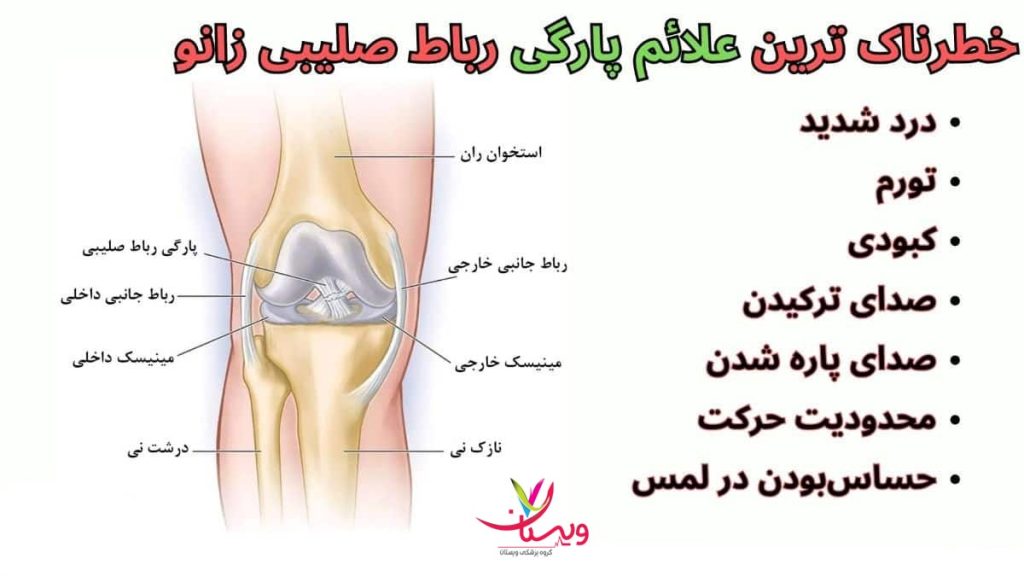

علائم پارگی رباط زانو

در بسیاری از موارد، افراد آسیبدیده به علائم پارگی رباط زانو بیتوجهی میکنند یا آن را با کشیدگی عضله یا ضربدیدگی ساده اشتباه میگیرند. این علائم پارگی رباط زانو در حالی است که تشخیص زودهنگام و اقدام به درمان میتواند از عوارض جدیتری همچون ناپایداری دائمی مفصل یا آرتروز پیشگیری کند.

- صدای تق تق یا پاپ در زمان آسیب یکی از بارزترین علائم پارگی رباط زانو، شنیدن صدایی شبیه به «پاپ» یا «تق تق» در لحظه آسیب است. این صدا معمولاً در پارگی رباط صلیبی قدامی (ACL) شنیده میشود و نشاندهنده گسستن ناگهانی الیاف رباط است.

- درد ناگهانی و شدید پس از پارگی رباط، معمولاً درد بهصورت ناگهانی و شدید در ناحیه زانو ظاهر میشود. این درد ممکن است در هنگام ایستادن، حرکت یا حتی در حالت استراحت نیز ادامه داشته باشد.

- تورم زانو یکی دیگر از علائم پارگی رباط زانو، تورم سریع زانو در عرض چند ساعت پس از آسیب است. این تورم به دلیل خونریزی داخلی ناشی از پارگی رباط ایجاد میشود.

- ناپایداری مفصل زانو احساس شلی یا ناپایداری در زانو، بهویژه هنگام راه رفتن یا دویدن، از علائم پارگی رباط زانو است. فرد ممکن است احساس کند زانویش میخواهد از زیر بدنش خالی شود.

- محدودیت حرکتی زانو پارگی رباط زانو میتواند باعث محدود شدن دامنه حرکتی مفصل شود. بیمار در خمکردن یا صافکردن زانو دچار مشکل میشود و گاهی حتی نمیتواند پای خود را بهدرستی روی زمین بگذارد.

- قفل شدن یا گیر کردن زانو از علائم شایع پارگی مینیسک، قفل شدن یا گیر کردن زانو هنگام حرکت است. این علامت بهخصوص در آسیب مینیسک داخلی مشاهده میشود و بهدلیل گیر افتادن قطعهای از غضروف بین استخوانها است.

- کبودی اطراف زانو کبودی در اطراف زانو، بهویژه در پشت یا کنار زانو، میتواند علائم پارگی رباط زانو از خونریزی داخلی و آسیب به رباطها باشد. این علامت معمولاً چند ساعت پس از آسیب ظاهر میشود.